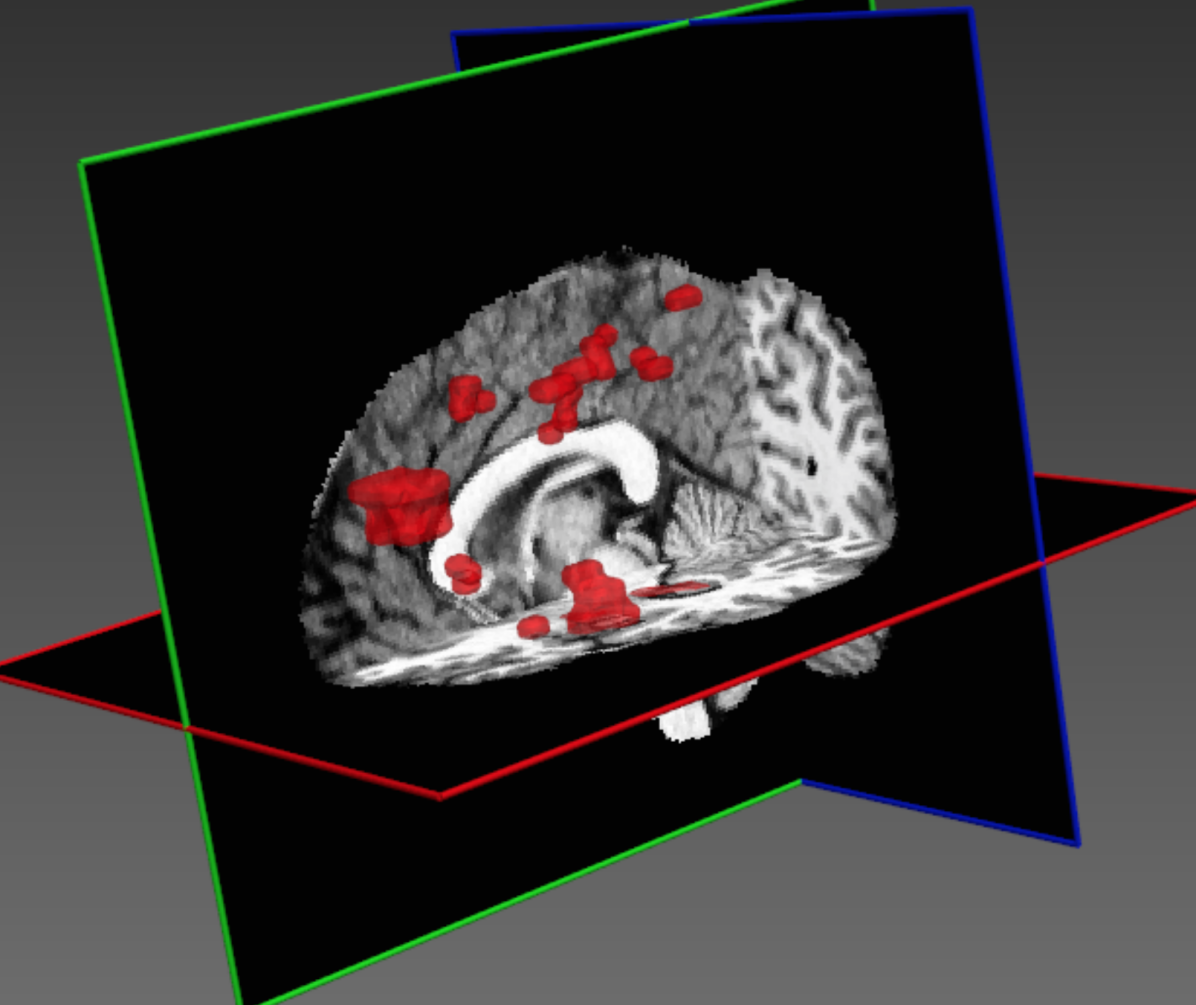

Figure 1 illustrates some of the challenges that arise when devising a computational approach for the task of automatic lesion segmentation. The figure summarizes statistics and shows examples of brain lesions in the case of TBI, but is representative of other pathologies such as brain tumors and ischemic stroke. Lesions can occur at multiple sites, with varying shapes and sizes, and their image intensity profiles largely overlap with non-affected, healthy parts of the brain or lesions which are not in the focus of interest. For example, stroke and MS lesions have a similar hyper-intense appearance in FLAIR sequences as other WMLs (Mitra et al. (2014); Schmidt et al. (2012)). It is generally difficult to derive statistical prior information about lesion shape and appearance. On the other hand, in some applications there is an expectation on the spatial configuration of segmentation labels, for example there is a hierarchical layout of sub-components in brain tumors. Ideally, a computational approach is able to adjust itself to application specific characteristics by learning from a set of a few example images.

Figure 8 shows the improvement DeepMedic achieves over the single pathway model Deep+. In Fig. 9 we show two representative visual examples of this improvement when using the multi-scale CNN. Finally, we confirm that the performance increase can be accounted to the additional context and not the additional capacity of DeepMedic. To this end, we build a big single-scale model by doubling the FMs at each of the 9-layers of Deep+ and adding two hidden layers. This 11-layers deep and wide model, referred to as “BigDeep+”, has the same number of parameters as DeepMedic. The performance of the model is not improved, while showing signs of over-fitting.

Table 1 summarizes the results on TBI. Our CNN significantly outperforms the Random Forest baseline, while the relatively overall low DSC values indicate the difficulty of the task. Due to randomness during training the local minima where a network converges are different between training sessions and some errors they produce differ (Choromanska et al. (2015)). To clear the unbiased errors of the network we form an ensemble of three similar networks, aggregating their output by averaging. This ensemble yields better performance in all metrics but also allows us to investigate the behaviour of our network focusing only on the biased errors. Fig. 10 shows the DSC obtained by the ensemble on each subject in relation to the manually segmented and predicted lesion volume. The network is capable of segmenting cases with very small lesions, although, performance is less robust in these cases as even small errors have large influence on the DSC metric. Investigation of the predicted lesion volume, which is an important biomarker for prognostication, shows that the network is neither biased towards the lesion nor background class, with promising results even on cases with very small lesions. Furthermore, we separately evaluate the influence of the post-processing with the fully connected CRF. As shown in Table 1, the CRF yields improvements over all classifiers. Effects are more prominent when the performance of the primary segmenter degrades, which shows the robustness of this regulariser. Fig. 11 shows three representative cases.

The performance of our system on the training data is shown in Table 4. Significant improvement is achieved by the structural regularisation offered by the CRF, although it could be partially accounted for by overfitting the training data during the CRF’s configuration. Examples for visual inspection are shown in Fig. 13.

The discriminative power of the learned features is indicated by the success of recent CNN-based systems in matching human performance in domains where it was previously considered too ambitious (He et al. (2015); Silver et al. (2016)). Analysis of the automatically extracted information could potentially provide novel insights and facilitate research on pathologies for which little prior knowledge is currently available. In an attempt to illustrate this, we explore what patterns have been learned automatically for the lesion segmentation tasks. We visualize the activations of DeepMedic’s FMs when processing a subject from our TBI database. Many appearing patterns are difficult to interpret, especially in deeper layers. In Fig. 14 we provide some examples that have an intuitive explanation. One of the most interesting findings is that the network learns to identify the ventricles, CSF, white and gray matter. This reveals that differentiation of tissue type is beneficial for lesion segmentation. This is in line with findings in the literature, where segmentation performance of traditional classifiers was significantly improved by incorporation of tissue priors (Van Leemput et al. (1999); Zikic et al. (2012)). It is intuitive that different types of lesions affect different parts of the brain depending on the underlying mechanisms of the pathology. A rigorous analysis of spatial cues extracted by the network may reveal correlations that are not well defined yet.

Similarly intriguing is the information extracted in the low-resolution pathway. As they process greater context, these neurons gain additional localization capabilities. The activations of certain FMs form fields in the surrounding areas of the brain. These patterns are preserved in the deepest hidden layers, which indicates they are beneficial for the final segmentation (see two last rows of Fig. 14). We believe these cues provide a spatial bias to the system, for instance that large TBI contusions tend to occur towards the front and sides of the brain (see Fig. 1(c)). Furthermore, the interaction of the multi-resolution features can be observed in FMs of the hidden layer that follows the concatenation of the pathways. The network learns to weight the output of the two pathways, preserving low resolution in certain parts and show fine details in others (bottom row of Fig. 14, first three FMs). Our assumption is that the low-resolution pathway provides a rough localization of large pathologies and brain areas that are challenging to segment, which reserves the rest of the network’s capacity for learning detailed patterns associated with the detection of smaller lesions, fine structures and ambiguous areas.